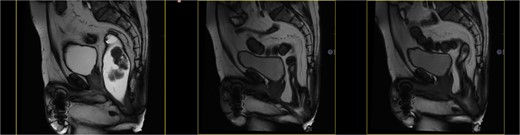

Dynamic MRI: Important rectal prolapse and pelvic floor descent. The evacuation after the introduction of the endorectal contrast was incomplete. (Fig. 2)

Dynamic MRI: Important rectal prolapse and pelvic descent without changes. The evacuation after the introduction of the endorectal contrast was complete (Fig. 3).